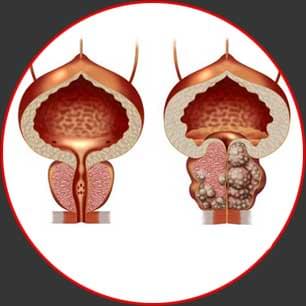

Du hast jedes halbes Jahr oder einmal im Jahr ein Engegefühl in der Leistengegend.

Du bemerkst, dass du öfters auf die Toilette gehst.

Du erfährst Schwierigkeiten beim Wasserlassen.

Beseitigt die Ursache von Prostatitis. Normalisiert das Wasserlassen, stellt eine Erektion wieder her

Dumpfe Schmerzen in der Leiste und im Skrotum. Adenom, Entzündung. Die Diagnose: „Prostatitis“. Ich hab mich

auf die OP vorbereitet. Aber als ich geschäftlich in Frankfurt war, bin ich in eine Klinik gegangen. Ich

wurde untersucht. Man hat mir Prostatricum verschrieben.

Nach 2 Monaten ist alles in Ordnung . Beim Pinkeln ist alles normal, es tut nichts weh, sticht nicht...